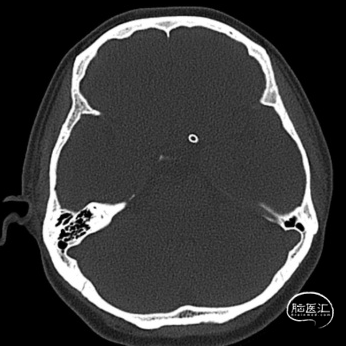

术后复查头部CT可见Surpass Streamline FD全程无狭窄,贴壁满意。患者无神经功能缺损表现,医嘱离院。